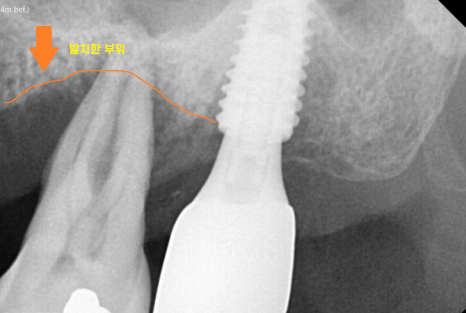

유독 안좋은 부위를

작은 x-ray를 찍어 추가 검사해보았더니..

오른쪽 윗 어금니 치아

잇몸 내려감이 관찰되었습니다.

정확하게 말해서는 잇몸 뼈가 내려간거죠